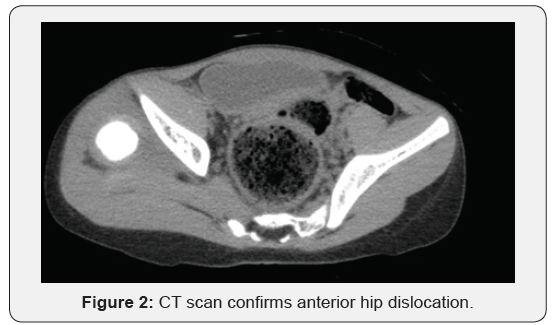

Physical examination revealed prominent limping on ambulation, positive Galeazzi sign (Figure 1), femoral head could be palpated in the right groin region, and the girl was pain free throughout her right hip range of motions. She had generalized join laxity and muscle hypotonia. Radiological examination confirmed right hip dislocation. CT scan demonstrated anterior position of femoral head, shallow acetabulum with severe anterior and posterior wall deficiency (Figures 2 & 3), and signs of soft tissue interposition. Acetabulum index was measured as 33 degree (Figure 4) and femoral anteversion as 70 degree.